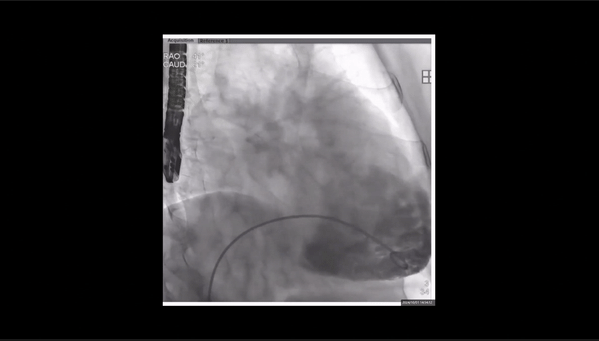

夾持件位置確認(rèn)

室間隔位置確認(rèn)

瓣膜釋放